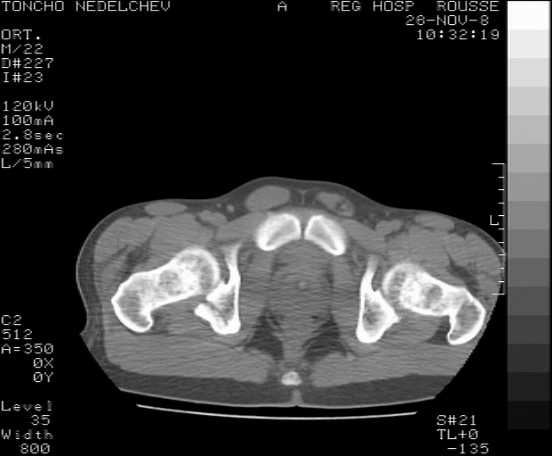

The details of the fracture are not so clear from the images sent...would you be able to send along an AP and Judet images as well as some additional axial images above and below the joint?

I’m not so sure that your patient has a Tr+PW pattern based on the images sent...maybe the fracture’s exact name won’t matter in the long run, but it’d be great to see enough images to make an accurate comment.

Without complete CT images and/or oblique radiographs, it's difficult to answer your question definitively, but it appears that there may not be a posterior wall fracture that requires a posterior approach. A successful reduction through an ilio-inguinal approach will have a faster recovery, and not risk SGN injury or heterotopic ossification.

Here are some more axial images. What is your opinion as for the timing of the operative treatment?